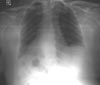

A chest radiograph is interpreted as normal; however, it is later noted that the "R" indicator is backward on the film. A second chest radiograph shows that the heart silhouette and gastric bubble are on the right and the elevated hemidiaphragm is on the left (Figure 2). This prompts a working diagnosis of situs inversus.